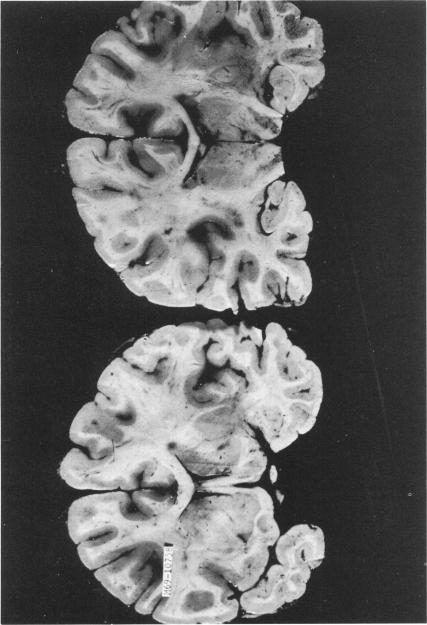

Neurological complications of addiction to heroin.

Bull N Y Acad Med. 1973 Jan;49(1):3-21.